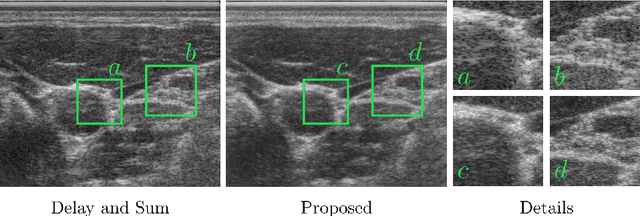

Abstract:Ultrasound imaging is caught between the quest for the highest image quality, and the necessity for clinical usability. Our contribution is two-fold: First, we propose a novel fully convolutional neural network for ultrasound reconstruction. Second, a custom loss function tailored to the modality is employed for end-to-end training of the network. We demonstrate that training a network to map time-delayed raw data to a minimum variance ground truth offers performance increases in a clinical environment. In doing so, a path is explored towards improved clinically viable ultrasound reconstruction. The proposed method displays both promising image reconstruction quality and acquisition frequency when integrated for live ultrasound scanning. A clinical evaluation is conducted to verify the diagnostic usefulness of the proposed method in a clinical setting.